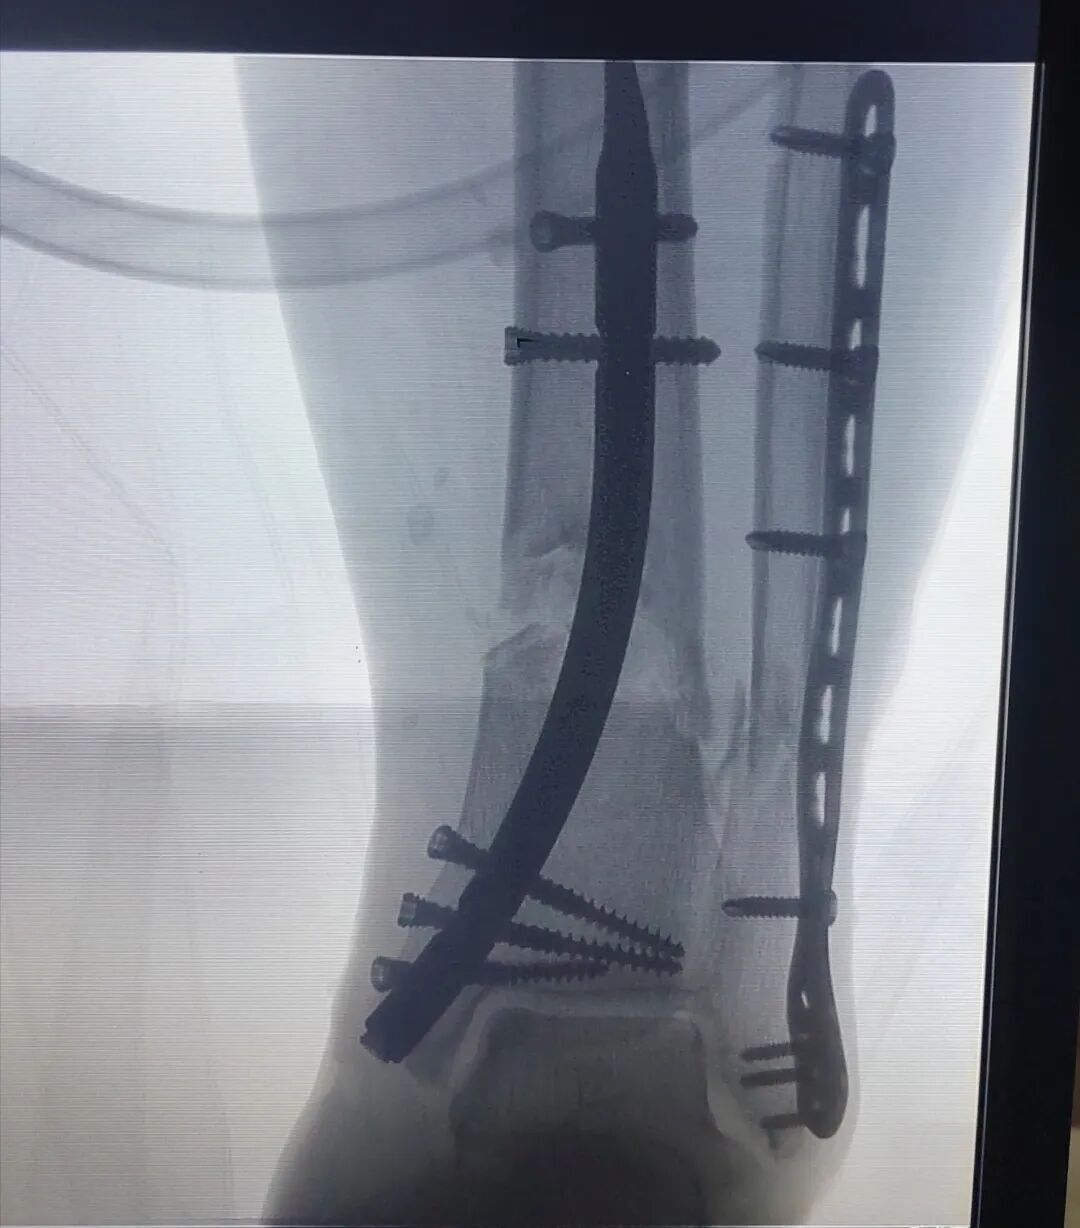

在与患者及家属充分沟通后,团队制定了周密的手术方案。术中,在C型臂X光机精准导航下,通过微创切口闭合复位骨折,顺利植入逆行髓内钉,并同期处理了合并的外踝骨折。手术过程流畅,出血不足50毫升。

图片

术中图像